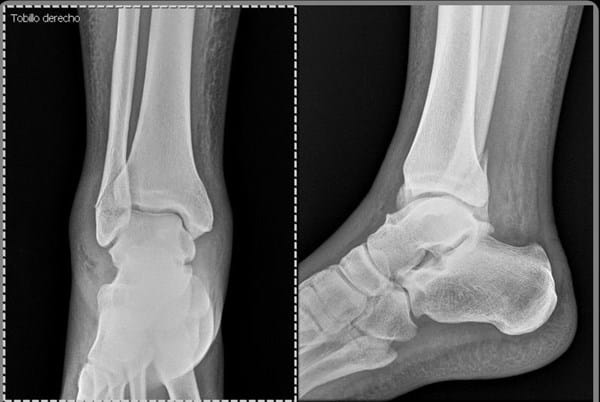

¿Qué opinan de mi fractura peroné?

Me quebré el día 20 de julio en una caída me dijeron que verán si se logra pegar el hueso con yeso o sino tendré que hacer cirugía. ¿Qué opinan?